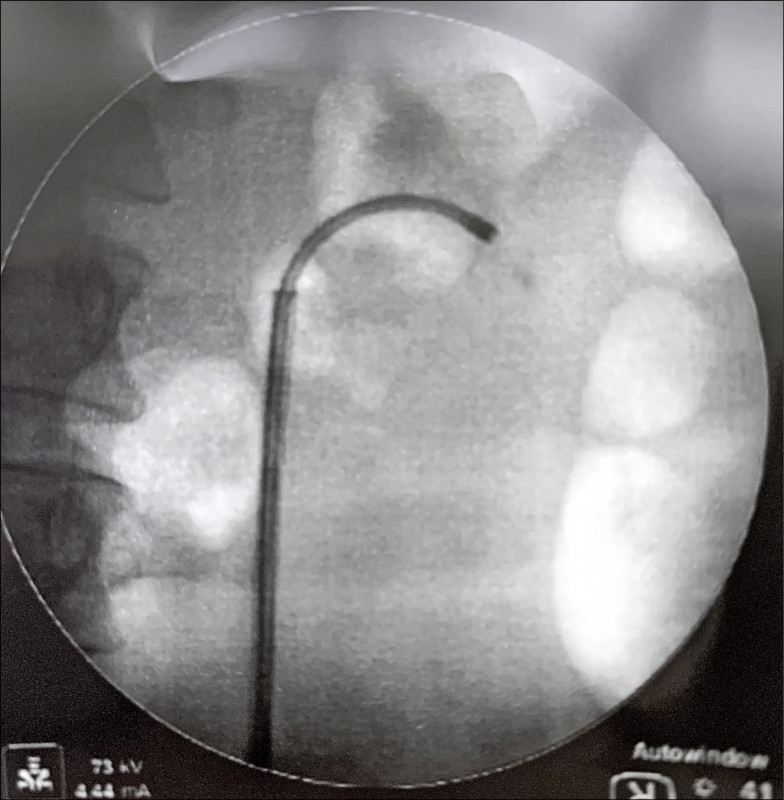

「微創手術」顧名思義就是利用微小的傷口來完成傳統上需要較大傷口才能完成的手術。泌尿科應用的微創手術有內視鏡、腹腔鏡、機器人手臂(達文西手術),不同手術的應用會對病人帶來不同的好處。

人體的泌尿器官由上而下依序為腎臟、輸尿管、膀胱、男性攝護腺與尿道,全部串連起來就是完整的泌尿系統。泌尿系統可能會發生許多疾病,例如:結石、腫瘤、發炎感染等,需要手術治療的疾病可以透過內視鏡,在不創造傷口的情況下,沿著尿道一路「逆流而上」,進入人體內將病灶移除,像是清除腎結石、切除膀胱內的腫瘤等,病人在進行內視鏡手術後,大部分於隔天就能出院回到原本的生活,不需要特別照顧傷口,或承受傷口帶來的疼痛。

隨著影像系統的發展,腹腔鏡也為外科手術帶來了重大的變革。傳統上,若要進行泌尿系統的腫瘤手術,如腎臟、膀胱或攝護腺切除,免不了要在身上開一道10-20公分的傷口;腹腔鏡的出現,讓手術只需要開4-5個1公分左右的傷口就能完成,不只減少了術中的出血量,也降低了術後的疼痛感,病人也能在術後更快下床活動,及早出院。

西元2000年以後,機器人手臂(達文西手術)發展迅速,為泌尿科微創手術帶來重大的轉變。藉由操作機器人手臂,器械可以深入骨盆底最深處,並透過機器手臂關節的應用,完成對傳統腹腔鏡手術而言,相對困難的膀胱尿道縫合術,使手術的成效大幅提升。